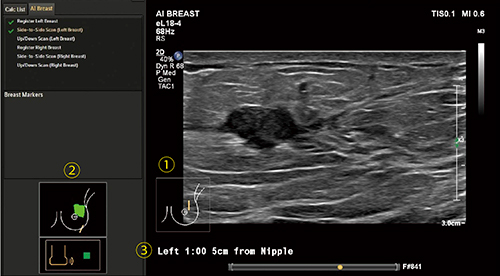

AI Breastでは,「超音波診断装置がトランスジューサの位置をリアルタイムで認識する」。これは,マットレスに内蔵された磁場発生装置「テーブルトップ型フィールドジェネレーター」(図3)とeL18-4に内蔵されたセンサである「電磁トラッキングコイル」により実現されている。従来の乳腺エコーの検査ワークフローを極力妨げずに,AI Breast機能が活用可能である。代表的な機能は下記である(図4)。

図4 AI Breast使用中の画面

(1) 自動で追従するプローブマーク,

(2) 走査軌跡のペイント,

(3) 乳頭腫瘤間距離の表示

1.自動で追従するプローブマーク

トランスジューサの位置が認識されているので,プローブマークの位置は自動で追従される。静止するたびに手作業で位置,角度を変更する従来の方法と比較して,プローブマークの間違いを減らすだけでなく,取り込んだ動画でもプローブマークが追従し位置情報を示す。

2.トランスジューサを走査したエリアを可視化

乳腺エコーでは,腋窩も含め広い範囲をスキャンしなければならないが,AI Breastでは,どの範囲でスキャンを行ったのか,走査の軌跡をペイントし,確認することができる。

3.乳頭からターゲットまでの位置と距離をワンタッチで表示

乳頭腫瘤間距離(以下,NTD)もワンタッチで表示することが可能である。乳頭からの位置が近ければ計測も簡便であるが,離れている際はデュアルやパノラマの機能を使用されている施設も多いかと思う。AI Breastでは,NTDが長い場合でも短時間で客観的な数値を表示することができる。